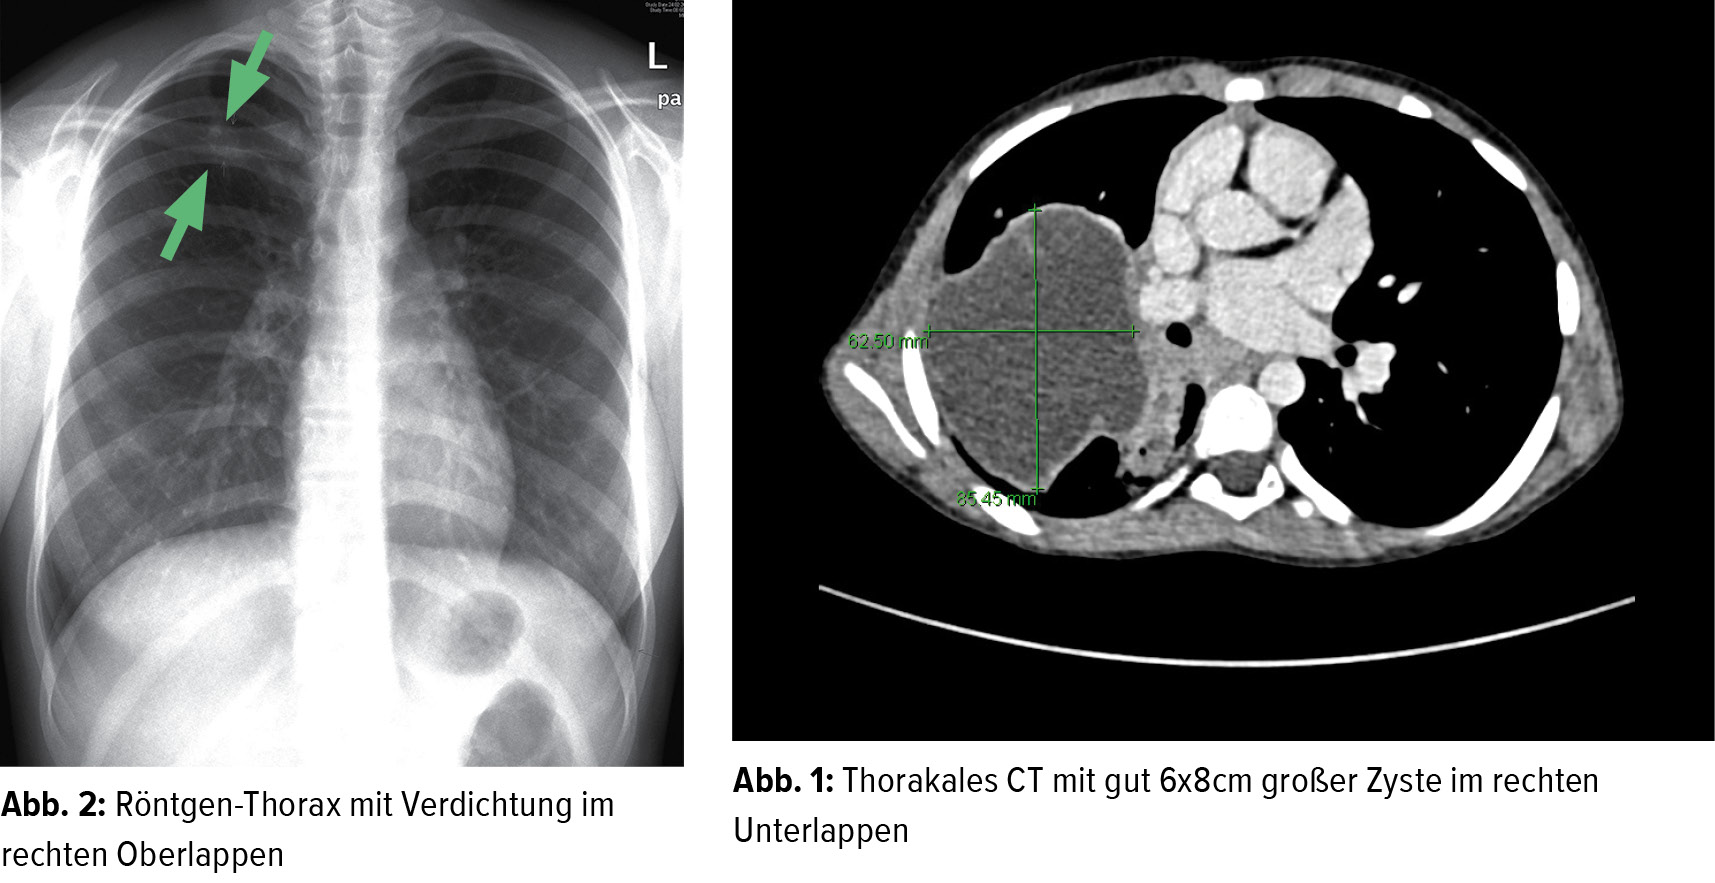

Vereinzelte Lungenzysten stellen bei älteren asymptomatischen Personen eine häufige altersbedingte Lungenveränderung dar Bei zystischen Lungenerkrankungen sind meist nur diffuse retikuläre Verschattungen erkennbar Die meisten befinden sich in den inneren Organen des Bauchraumes, vor allem in Niere und Leber

Lunger, metastase, CT 1 Lægehåndbogen på sundhed.dk. Solche Zysten erscheinen normalerweise in der Kindheit In der Lunge allerdings ist das anders: Lungenzysten sind dünnwandige Höhlen, die mit Luft gefüllt sind